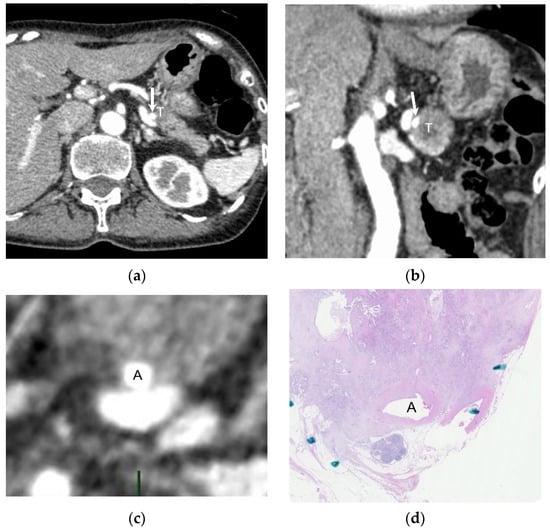

2.3. Creation of Perpendicular Reconstructed CT Images and Selection of Pathological Specimen

3.2. Pathological and Radiological Measurements of Solid Soft-Tissue Contact